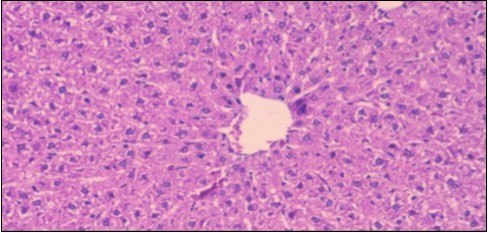

The histological examination of the kidney of the control rats fed on a standard diet showing normal rounded capsules with normal Bowman's glomeruli, round proximal tubules and elongated distal tubules with high cuboidal cells figure 1. The rats fed (HFD) showed fatty degeneration of the tubules with eosinophilic material deposition, glomerular atrophy with wide urinary space and distal tubules with extrusion of nuclei into lumen figure 2. By comparison kidneys of rats which were treated by fennel after being obese and the control rats observed partial improvement in both Bowman's capsules and proximal tubules. Note the distal tubules show less focal fatty infiltration figure 3.While examination of rats kidney that were treated by ator after obesity showed improvement in Bowman's capsules with normal glomerular and partial improvement in proximal tubules and distal tubules, figure 4. Kidney of rats that were treated by fennel and ator after obesity and the control rats showed high improvement in the tissues with normal glomerular and that Most of Bowman's capsules and renal tubules, restoring their normal appearance figure 5.

Figure 1.Photomicrogragh of kidney section of control rat showing normal rounded capsules with normal Bowman,s glomeruli, round proximal tubules and elongated distal tubules with high cuboidal cells , (H&E) (40X).

Photomicrogragh of  kidney section of          control rat showing normal rounded capsules with normal Bowman,s glomeruli, round proximal tubules  and elongated   distal tubules with high cuboidal cells , (H&E) (40X).